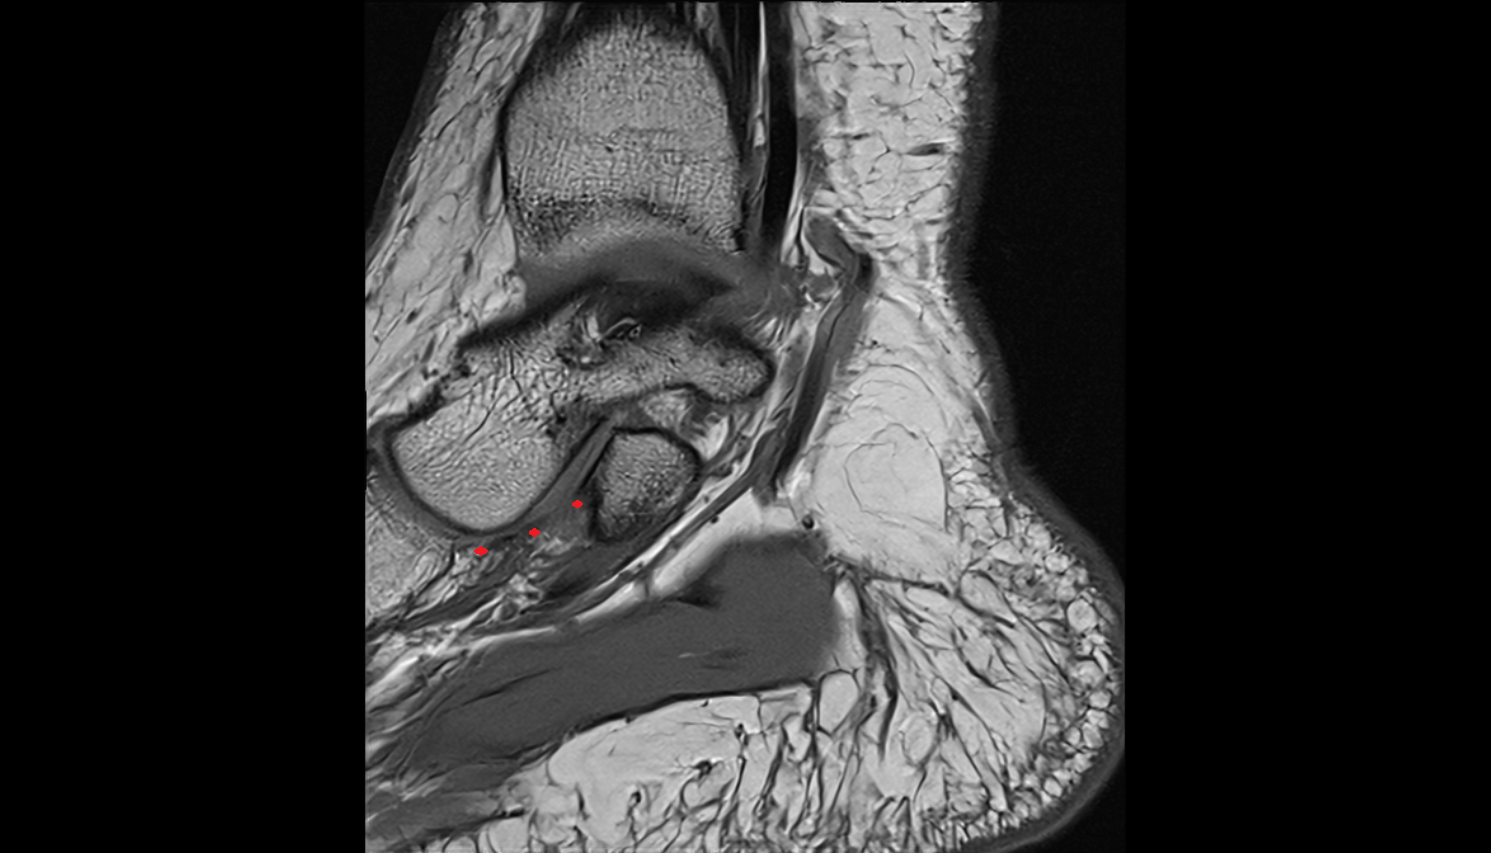

- Temporomandibular joint

- Articular disc of temporomandibular joint

- Articular eminence

- Mandibular condyle

- Mandibular fossa